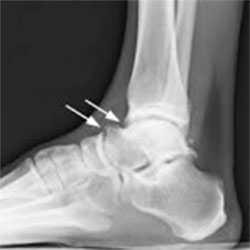

Рентгенография, КТ позволяют визуализировать краевые остеофиты и свободные внутрисуставные костные фрагменты.

Пациенту обязательно назначают рентгенограмму. На рентгенологическом снимке доктор легко увидит остеофиты - костные разрастания, появившиеся из-за воспалительного процесса. Дополнительно выполняется снимок в стрессовом положении. На нем доктор определит, есть ли соударение костей.

- Рентгенография плечевого сустава. Базовое исследование с достаточно низкой информативностью. Позволяет исключить некоторые патологии, установить размер субакромиального пространства, обнаружить остеофиты и участки кальцификации в мягких тканях.